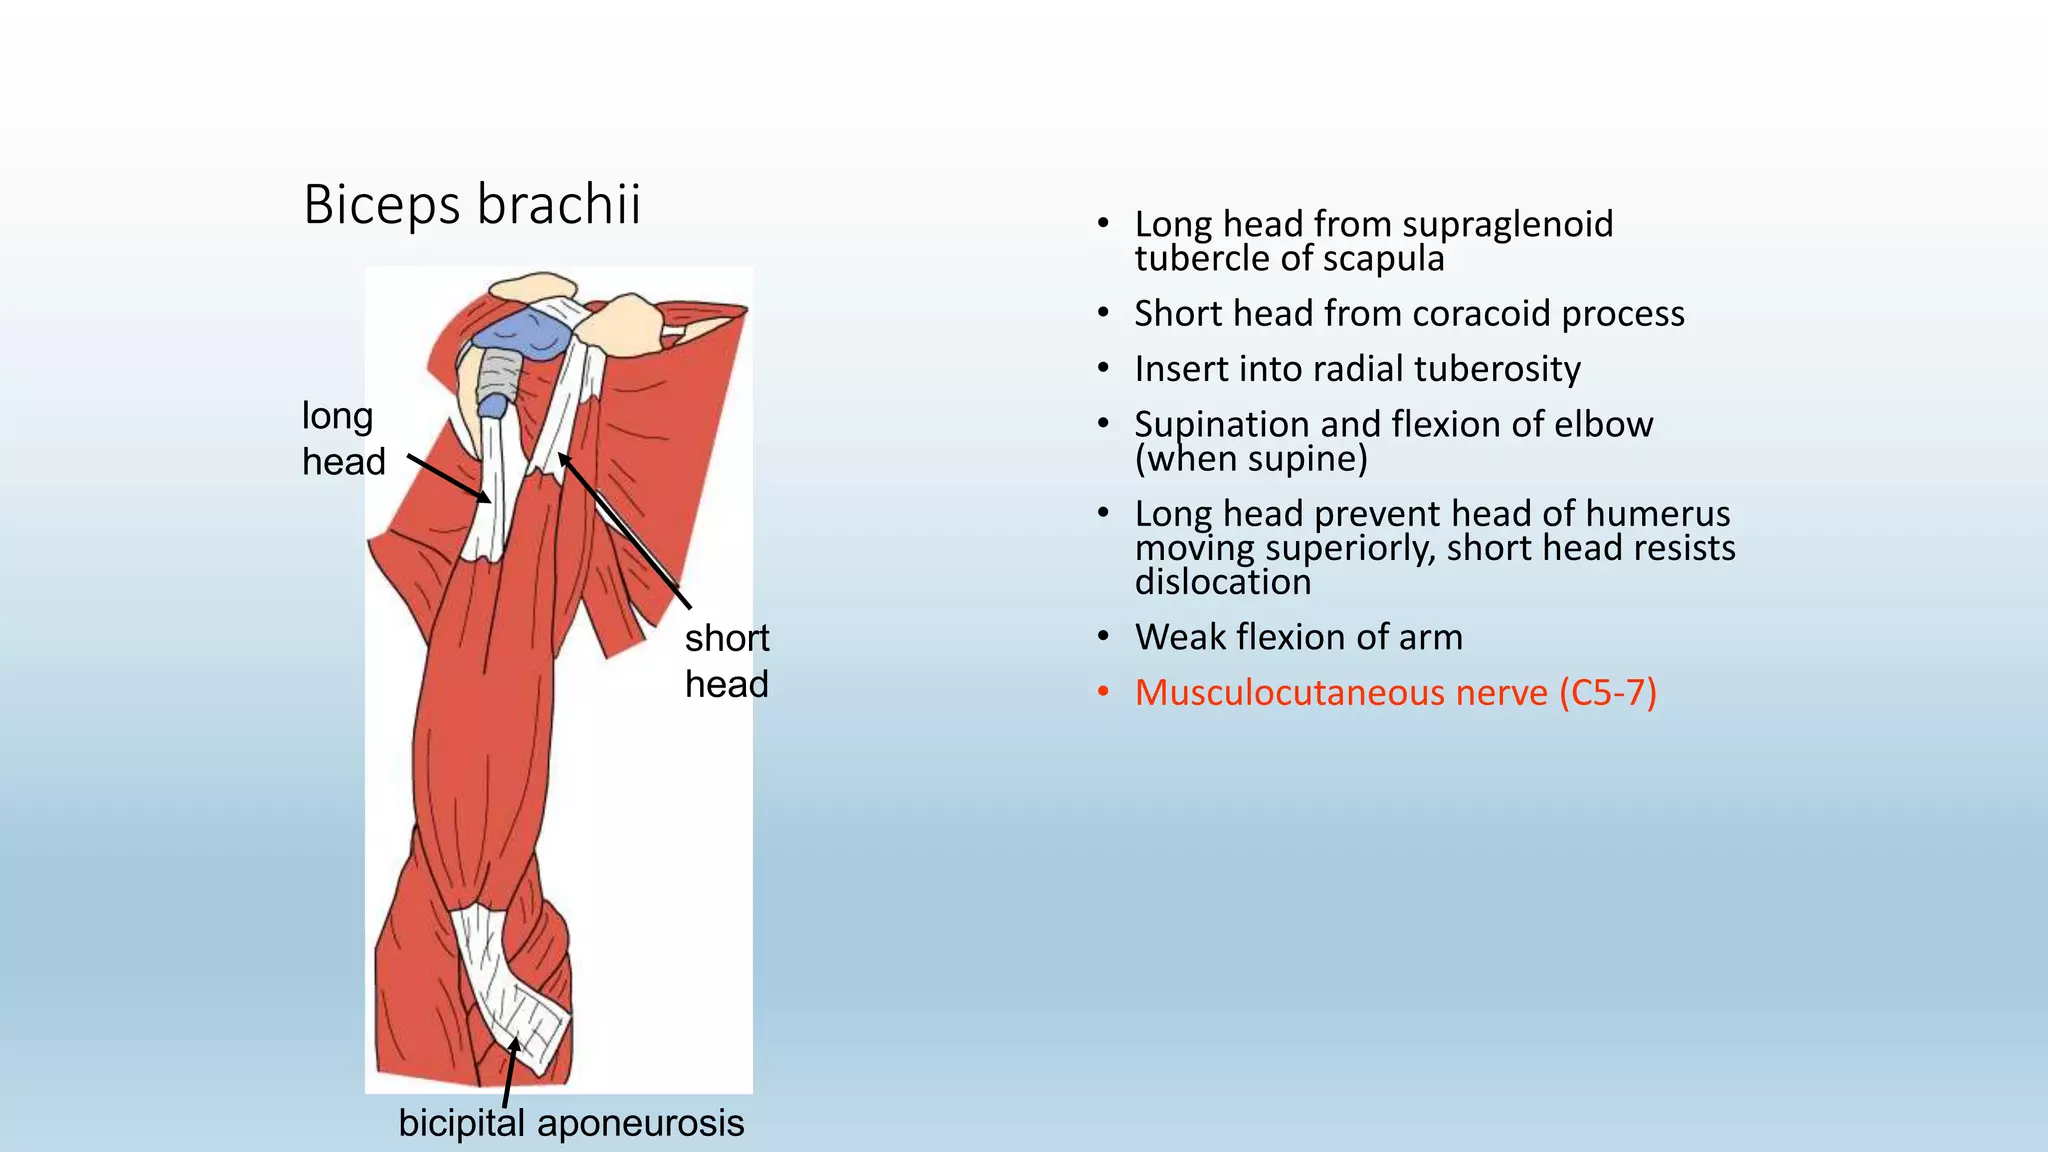

The document summarizes an anatomy revision session on the upper limb. It discusses various muscles of the upper limb including their origins, insertions, innervations and functions. Key muscles covered include the pectoralis major and minor, serratus anterior, deltoid, biceps brachii, brachialis, coracobrachialis, and triceps. It also discusses the rotator cuff muscles and muscles of the forearm including flexor carpi ulnaris and radialis. The session aims to help students identify upper limb muscles and understand their relations to nerves.